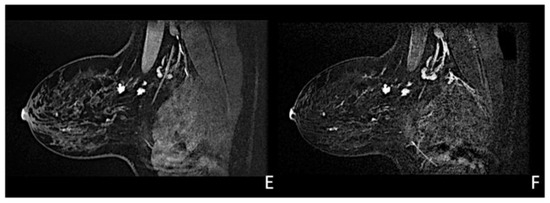

Figure 6.

Woman with a palpable mass of the outer left quadrants and a history of pruritic erythema of the ipsilateral nipple. A skin biopsy was performed with PC positivity. Unilateral craniocaudal (A) and oblique (B) mammograms of the left breast show diffuse fine pleomorphic microcalcifications (arrow) in the upper outer quadrant with architectural distortion associated. US detects multiple inhomogeneous hypoechogenic areas (arrow) with poorly defined margins and maximum diameter of 15 mm (yellow line) (C,D), corresponding to foci of non-mass-like enhancement with associated nipple enhancement (E,F). The patient underwent a left mastectomy, and high-grade invasive e multicentric ductal carcinoma was diagnosed.